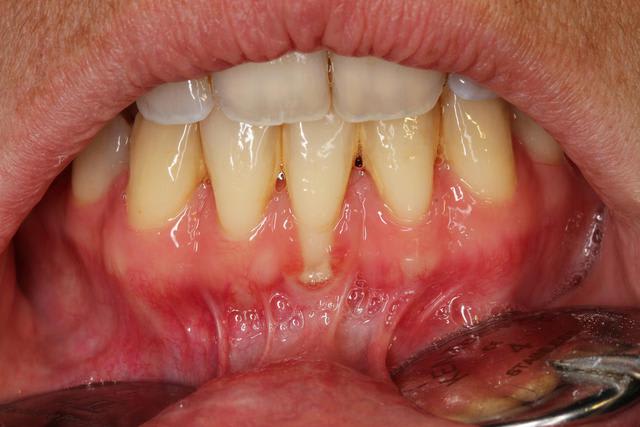

quel serait votre attitude thérapeutique sur une telle récession gingivale,avec brides et parodonte très fin.

Comme vous pouvez le constater, le tartre est assez présent: il reviens vite malgré un brossage général plutôt bon, sauf sur cette zone.

Il semble que les papilles soient larges donc lambeau bipapillaire why not ? Voir meme un lambeau déplacé latéralement en prenant la zone sect 3.

Sinon une GEC classique mais faudra aller assez pas dans la dissection et tu en profiterais pour sectionner toutes les fibres en éventail du frein.

Le parodonte n'est pas épais mais ne semble pas si fin que ca non plus.

Tu n'as pas de GA en apical de ta recession. Mobiliser lateralement les tissus gingivaux environnant t'oblige á faire du mutipapillaire.

Pour faire plus simple, je te conseille de faire une GGL en prenant soin de preparer correctement et suffisament ton lit receveur ( comme on a vu lors de la formation a laquelle tu avais assisté). Greffon adapté et sutures réflechies sont autant de facteurs qui te permettront a mon avis de recouvrir l'ensemble de la retraction sans deuxième intervention.